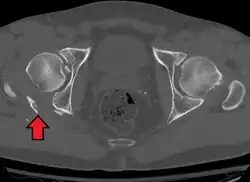

Axial CT image (viewed on bone windows) of a complex comminuted left acetabular fracture involving both anterior and posterior columns. -

Both column fracture showing floating weight bearing dome -